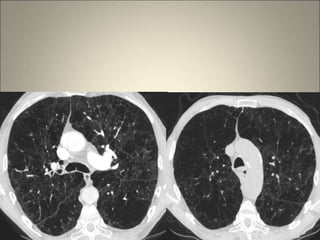

Association d’ECL et

d’EPS

Association d’EPL et

d’ECL

Difficultés parfois………..